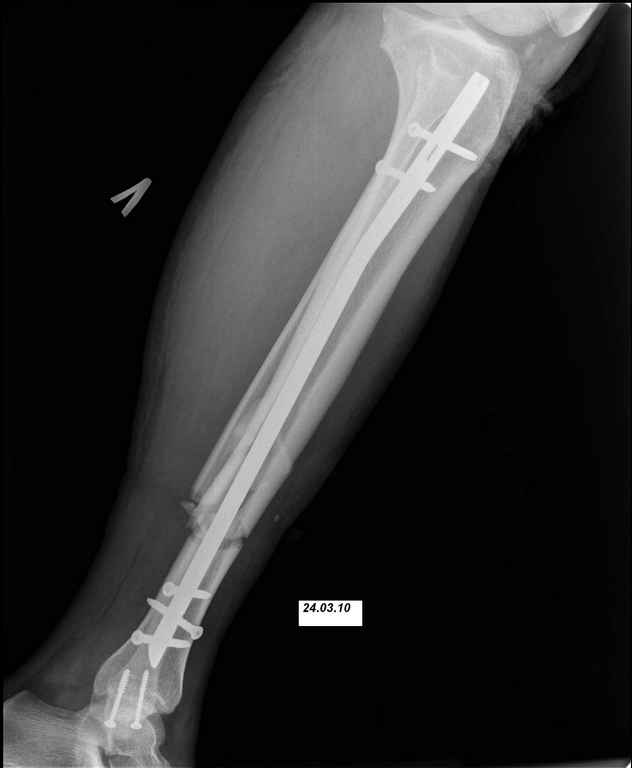

24.03.10 выполнены операции - БИОС перелома большеберцовой кости левой голени (штифт Synthes), остеосинтез перелома внутренней лодыжки левой голени винтами. Послеоперационный период протекал без осложнений. Выписан на 10 сутки. Амбулаторно не наблюдался.

Во первых штифт тонкий, во вторых коротккий. Не смотря на то что дистальное блокирование выполнено 3 винтами, связь с коротким дистальным отломком получиласть слабоватая если учесть активный образ жизни пациента и его "ненадежность" как выразился Александ Николаевич.

Здравствуйте Алексей Алексеевич. К сожалению, это самый "толстый" штифт который у нас есть (d10), и самый длинный (360мм). Пациент отправился на консультацию и возможное лечение к Александру Николаевичу. Административные барьеры не позволили воплотить в жизнь ни один из предложенных вариантов. Всем спасибо за комментарии и советы.